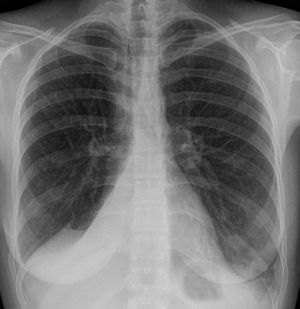

임상적으로 유의미한 무기폐는 일반적으로 흉부 엑스레이에서 관찰 가능하며, 폐의 불투명화 및/또는 폐 용적 감소와 같은 소견을 보일 수 있다. 수술 후 무기폐는 양쪽 기저부에서 나타나는 양상을 보인다. 무기폐의 원인이 임상적으로 명확하지 않은 경우 흉부 CT 또는 기관지 내시경이 필요할 수 있다.[10] 무기폐의 직접적인 징후로는 엽간 열구 및 흉강 내 이동성 구조의 변위, 영향을 받지 않은 동측 폐엽 또는 반대쪽 폐의 과도한 팽창, 그리고 허탈된 폐엽의 불투명화가 있다.[10] 흉부 엑스레이에서 임상적으로 유의미한 소견 외에도, 환자는 횡격막의 상승, 기관, 심장 및 종격동의 이동, 폐문의 변위 및 육아종의 이동과 같은 간접적인 징후와 증상을 나타낼 수 있다.[10]

- 흉부 엑스레이 사진